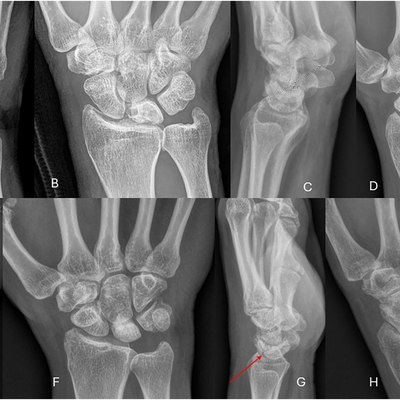

Click on an image below to view more info.